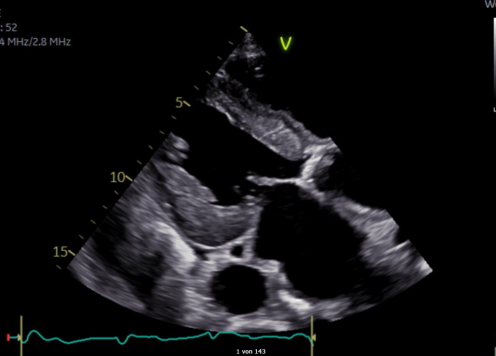

In den letzten Jahren hat sich das Feld der Echokardiographie deutlich weiterentwickelt. Durch zunehmend speziellere Fragestellungen wächst der Anspruch an das Verfahren stetig. Neben neuen Untersuchungsverfahren wie Strainbestimmung gehören mittlerweile aufwändige Messmethoden zur Beurteilungen von Klappenvitien auch im Hinblick auf mögliche neue therapeutische Verfahren immer mehr zum Alltag.

Neben dem Auffrischen der zentralen wichtigen Untersuchungsschritte sollen im Kurs spannende Fälle vorgestellt, die Einschätzung von Befunden im Grenzbereich diskutiert und neue Verfahren geübt werden. Dazu wird es neben anschaulichen Theorieblöcken viel Gelegenheit für praktische Übung unter Anleitung erfahrener Referenten geben, zum Teil auch unter Mithilfe modernster Technik mit Simulation von Befunderhebung und -auswertung am Laptop.